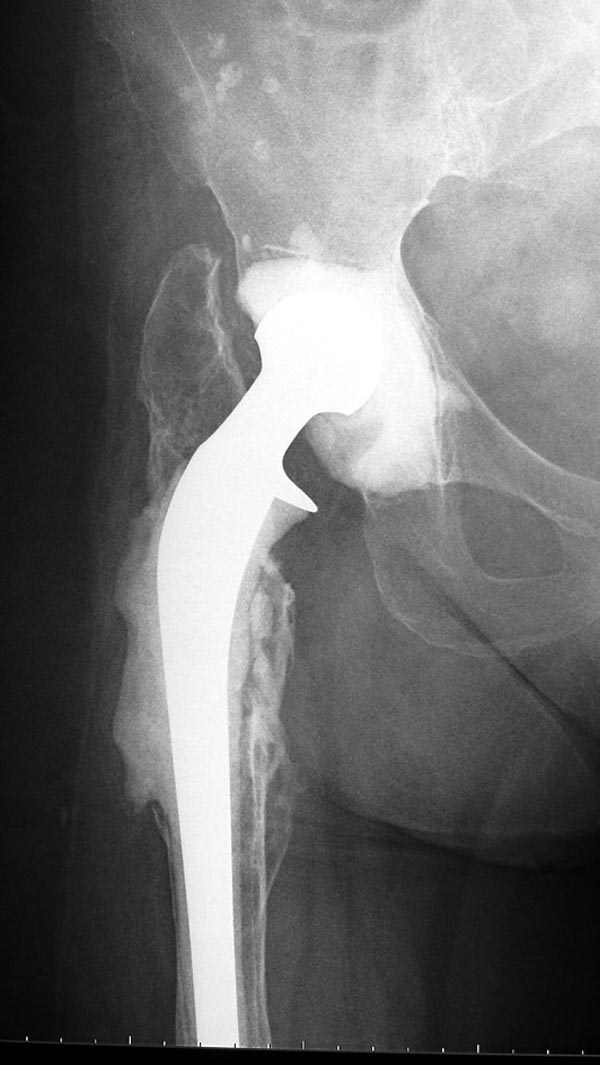

Следующий этап восстановление применением Blade Plate. Универсальный имплант и сегодня является уникальным по механическим характеристикам для восстановления проксимального отдела бедра где имеется сложная биомеханика.

Имеющиеся 130 градусные для вальгуса пластины от

Synthes короткие всего на две дырки, выход, обычная длинная 95 градусная Blade Plate разгибается до 105-110 градусов. Металл трудно поддается деформации, и его не согнуть между тепловой батереей в операционной, надо подготовить заранее после предварительного нагрева в механической мастерской.

Проведя клинок горизонтально в шейку, и соединив с

диафизом бедра создаем небольшой вальгус, тем самым увеличиваем длину конечности. Образовавшийся дефект кости надо заполнить блоком цемента, который предупреждает инфицирования и дает устойчивость конструкции. После затихания процесса можно приступить ко вторичному заполнению аутокостью или можно применить костную массу из того же местного костного регенерата.

Обещанный Synthesом локинг вариант пластины еще до нас не дошел, но блокирующая на пластине шайба поможет созданию локинг концепт.